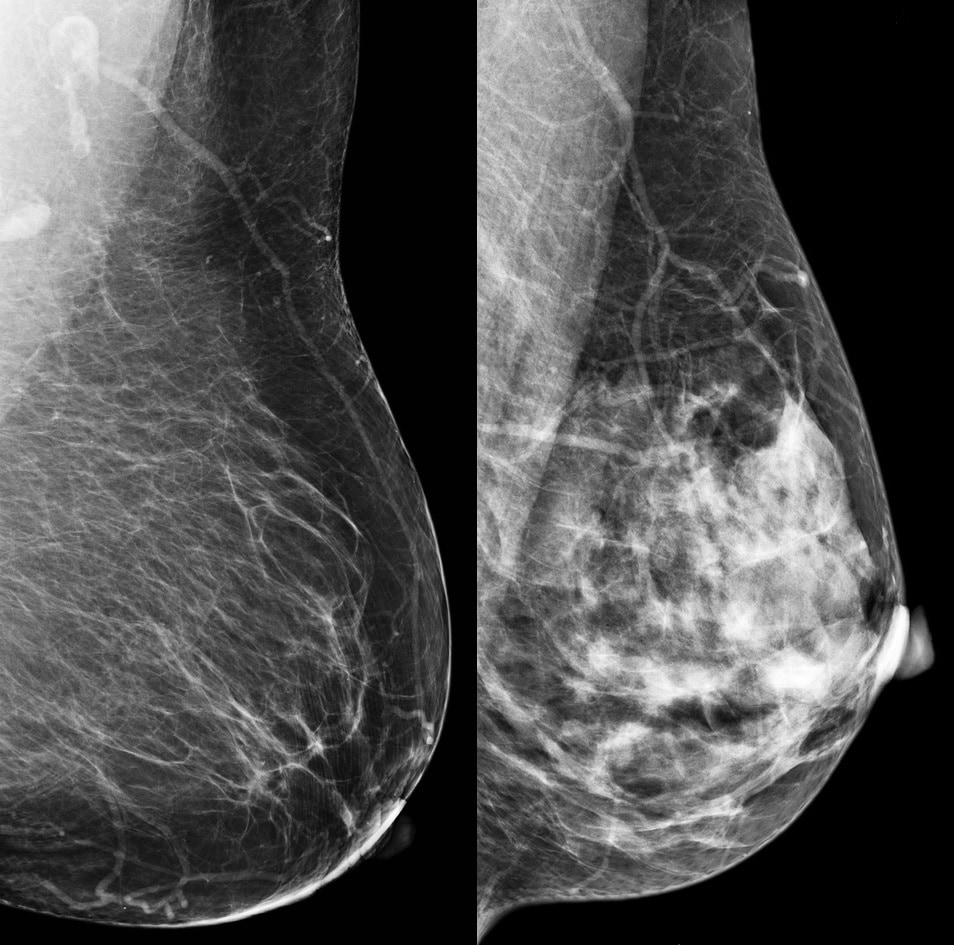

A mammogram shows how dense your breasts are. When you get the results of your mammogram, you may also be told if your breasts have low or high density. Women with dense breasts have a higher risk of getting breast cancer.

Breast density reflects the amount of fibrous and glandular tissue in a woman’s breasts compared with the amount of fatty tissue in the breasts, as seen on a mammogram.

Dense tissue can hide cancers. Fibrous and glandular tissue looks white on a mammogram. So does a possible tumor. Because it’s hard to tell the difference between a tumor and dense breast tissue on a mammogram, a small tumor may be missed.